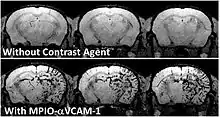

To achieve molecular imaging of disease biomarkers using MRI, targeted MRI contrast agents with high specificity and high relaxivity (sensitivity) are required. To date, many studies have been devoted to developing targeted-MRI contrast agents to achieve molecular imaging by MRI. Commonly, peptides, antibodies, or small ligands, and small protein domains, such as HER-2 affibodies, have been applied to achieve targeting. To enhance the sensitivity of the contrast agents, these targeting moieties are usually linked to high payload MRI contrast agents or MRI contrast agents with high relaxivities.[2] In particular, the recent development of micron-sized particles of iron oxide (MPIO) allowed to reach unprecedented levels of sensitivity to detect proteins expressed by arteries and veins.[3]